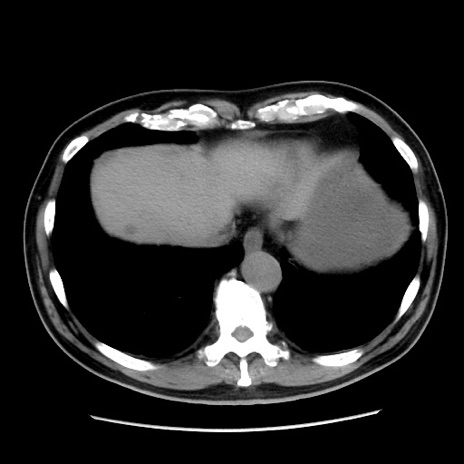

冠状断像